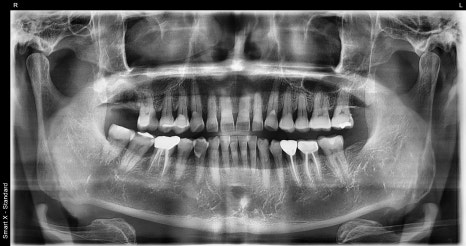

파노라마 검사와 CT 촬영을 통해

정밀 확인을 진행했습니다.

검사 결과는 단순한 충치나

크라운 파절이 아닌 치근 부위까지

금이 발생한 상태였습니다.

금이 뿌리 끝까지 뻗어 있는 경우에는

보존치료로 살리기 어렵고,

발치 후 임플란트 시술을 고려해야 합니다.

또한 위 어금니는 상악동과 가깝기 때문에,

뼈가 얇거나 염증이 심하면 뼈이식이나

상악동 거상이 함께 필요한 경우가 많습니다.